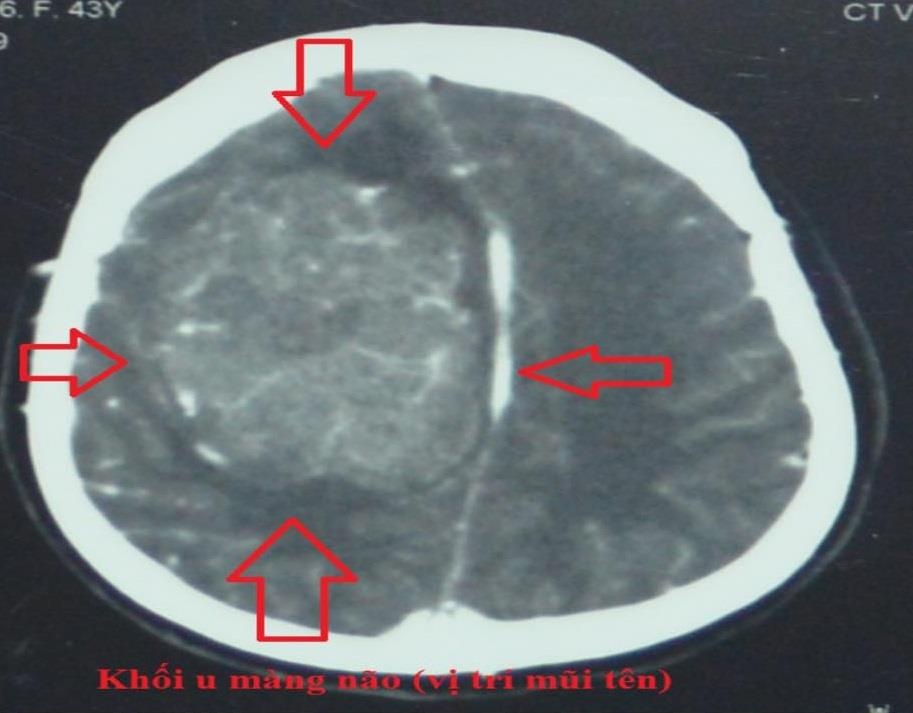

Sau khi nhập viện, các bác sĩ tiến hành thăm khám và kiểm tra, kết quả cho thấy bệnh nhân bị u màng não bên phải với kích thước 5x8 cm. Với tình trạng động kinh, nhiều bệnh nội khoa phức tạp, khối u nằm ở vị trí vùng vận động, bệnh nhân có thể liệt tay, chân nếu không xử trí tốt.

| Hình ảnh khối u màng não lớn. Ảnh: BVCC |

BSCKI Nguyễn Đông Quân, khoa Ngoại Thần kinh, cho biết đây là trường hợp khó, khối u nằm ngay vị trí liềm não đoạn 1/3 giữa xoang tĩnh mạch dọc trên nên nguy cơ tổn thương xoang và các mạch máu đổ về xoang cao. Bệnh nhân có thể nhồi máu não sau mổ dễ dẫn đến tử vong.